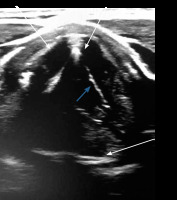

VF assessment in ultrasound can be done during routine USG before any thyroid surgery. During the ultrasound examination, a linear probe is placed transversely above the thyroid cartilage in the front as well as on the right and left side. The examination is painless and non-invasive. During breathing, coughing, swallowing, and phonation the symmetry, mobility, and position of the VFs is assessed. Usually it is easier to visualise false VFs (the body), which appear as thicker, hyperechoic bands in the shape of an inverted “V” (Figure 1) in comparison to true VFs (the cover), which are much thinner and more hyperechoic (Figure 2).